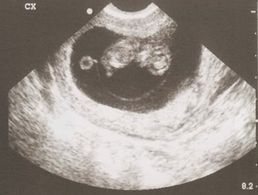

La ilusión de la primera ecografia

En España son tres ecografías las indicadas, una en cada trimestre para confirmar que todo está bien. Empiezas a leer y escuchar todo tipo de experiencias, lo que es posible que te lleve a plantearte hacerte una primera ecografía por el seguro privado, antes de la semana 12 (la primera indicada por la seguridad social).Si estás en ese momento de incertidumbre...te invito a que leas el post de esta bloguera-madre-maestra que habla sobre sus motivos por los que esperar a hacérsela a la semana 12:  ¿Por qué no me haré ecografías antes de la semana 12?Espero que este enlace os pueda ayudar a decidir, decidáis lo que decidáis estará bien, y sobre todo estaréis más informados. FELICIDADES!!!